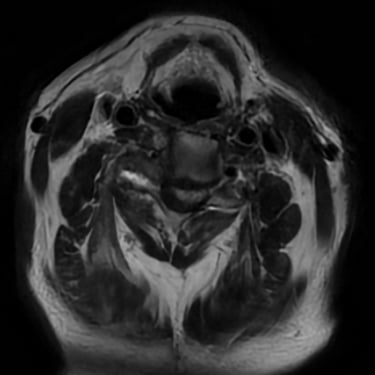

🧠 Cuerpo Extraño en la Región Posterior del Cuello | Cirugía Cervical.

La extracción de un cuerpo extraño en la región posterior del cuello requiere una cuidadosa cirugía cervical, guiada por estudios de imagen. Con técnicas microquirúrgicas se logra retirar el objeto de forma segura, preservando nervios y tejidos cervicales, y garantizando una recuperación adecuada sin comprometer la función neurológica.